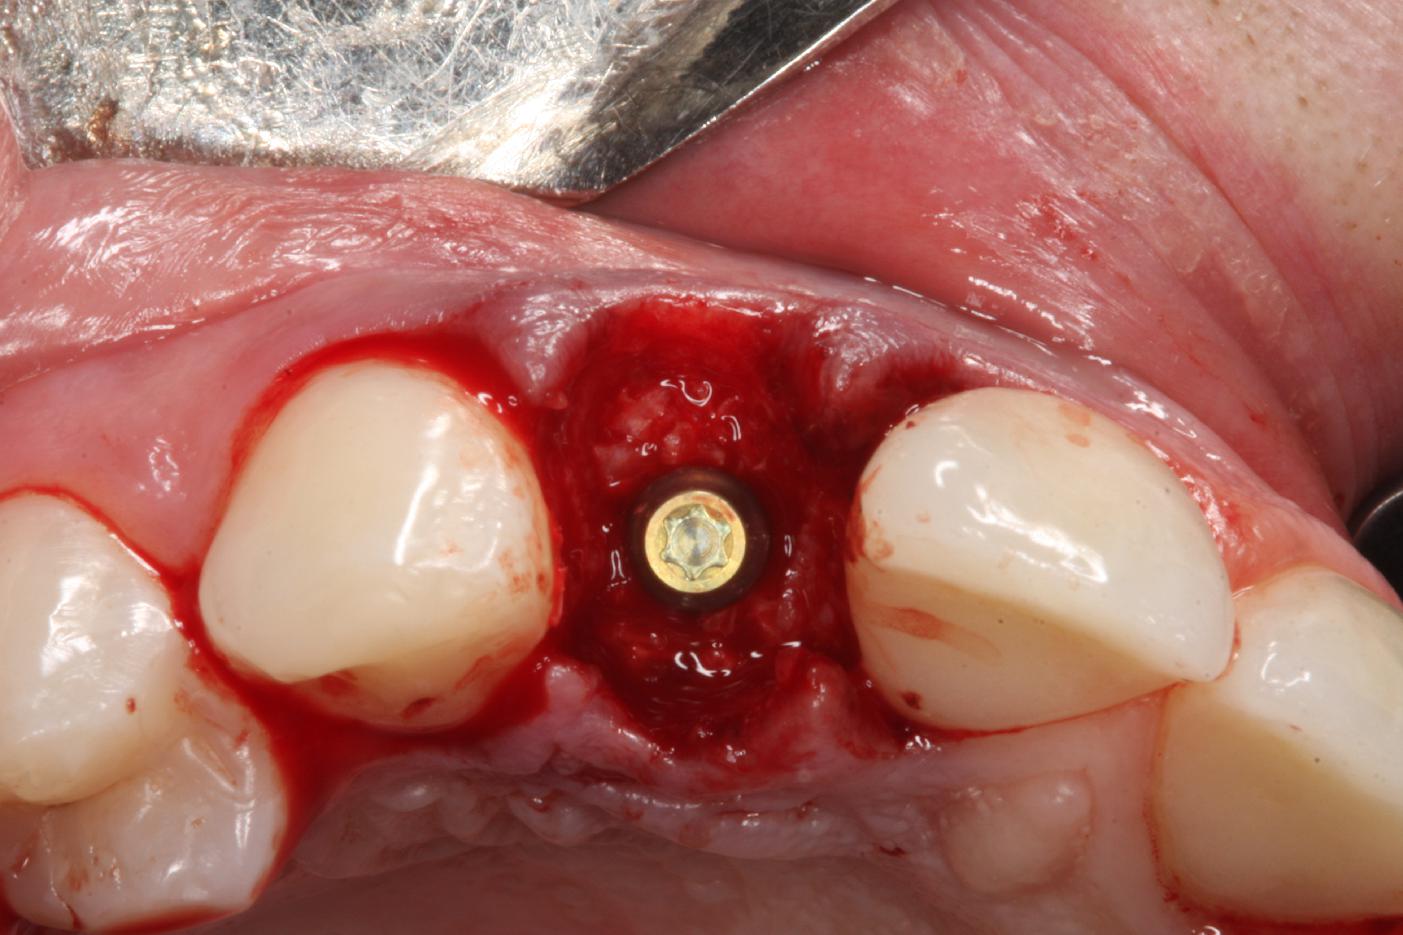

5/12 - Covering of immediate placed implant and augmentation with maxgraft® granulesSoft tissue thickening at immediate implant placement and GBR with mucoderm® and maxgraft® - Dr. A. Puisys